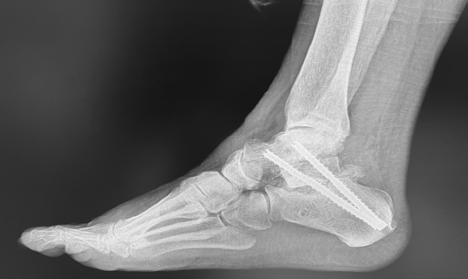

Subtalar arthrodesis (SA) is a common surgical procedure for patients with posttraumatic subtalar joint arthritis resulting from a fractured calcaneus. When performing subtalar arthrodesis, the surgeon aims to stabilize the subtalar joint to alleviate pain and restore function. While SA is an effective option, complications such as nonunion can occur. The reported nonunion rates in the literature can vary widely due to factors like patient characteristics and surgical techniques. Screw fixation is the standard approach for SA, but debate exists over the optimal number and configuration of screws used.1 An angulated screw configuration (SC) has been proposed as potentially superior than the traditional parallel SC, offering greater stability and resistance to rotational forces. The authors of a recent study note that historically, angulated SC shows promising results, but comparative research in clinical settings is limited.1

An emerging study aimed to compare the outcomes of SA using parallel and angulated SCs for posttraumatic subtalar joint arthritis. It involved 140 cases, with 80 using parallel SC and 60 using angulated SC.1 The nonunion rate was significantly lower in the angulated SC group (5.0%) compared to the parallel SC group (17.5%). Patients in the angulated SC group also reported better functional outcomes and lower pain scores. Although both groups had similar demographics and surgical characteristics, the angulated SC group showed superior results.